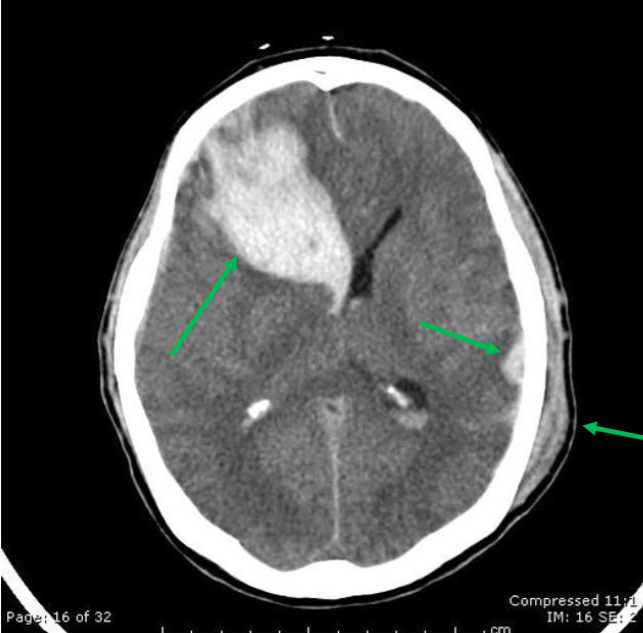

腦實質出血 (Intraparenchymal hemorrhage)

image

顱內血腫 (Intracerebral hematoma)

• 也可能是亞急性或延遲性